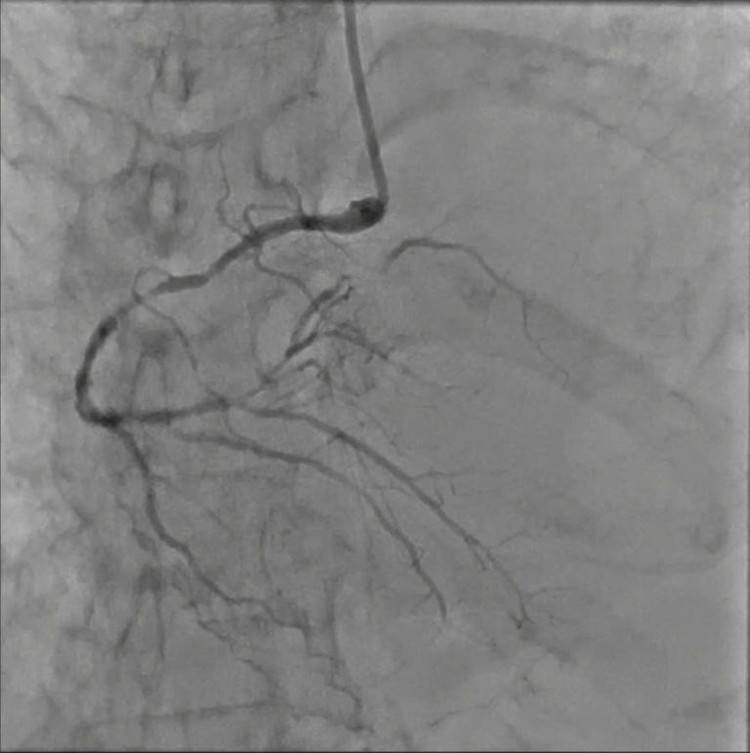

Với sự quyết tâm của gia đình, ekip can thiệp đã nhanh chóng tiến hành chụp, nong và đặt stent động mạch vành cho người bệnh. Quá trình can thiệp chụp DSA cho thấy người bệnh bị bệnh mạch vành 3 nhánh, hẹp nặng 70% – 80% nhánh bên phải từ đoạn gốc đến đoạn xa, hẹp 80% – 90% cả 2 nhánh bên trái.

Bệnh nhân được tiến hành đặt 2 stent cùng lúc vào 2 nhánh bên trái. Sau can thiệp tình trạng huyết động bệnh nhân dần ổn định, ngưng được thuốc vận mạch và rút ống thở sau 2 ngày điều trị tại Khoa Hồi Sức Tích Cực. Sau đó, bệnh nhân tỉnh táo hoàn toàn, không yếu liệt, không khó thở, không đau ngực, vận động gắng sức tốt và chuẩn bị có thể ra viện.

| Hình ảnh trước và sau can thiệp - Ảnh: BVCC |

Đặc biệt, người bệnh có tổn thương mạch máu khá đặc trưng của người bệnh đái tháo đường, đó là tổn thương cả ba nhánh mạch vành, kể cả tổn thương ở những mạch máu nhỏ kèm biến chứng phù phổi cấp. Do đó, ekip đã tiến hành can thiệp đồng thời 2 nhánh hẹp nặng nhánh liên thất trước và nhánh động mạch mũ để giải quyết tình trạng tắc nghẽn.